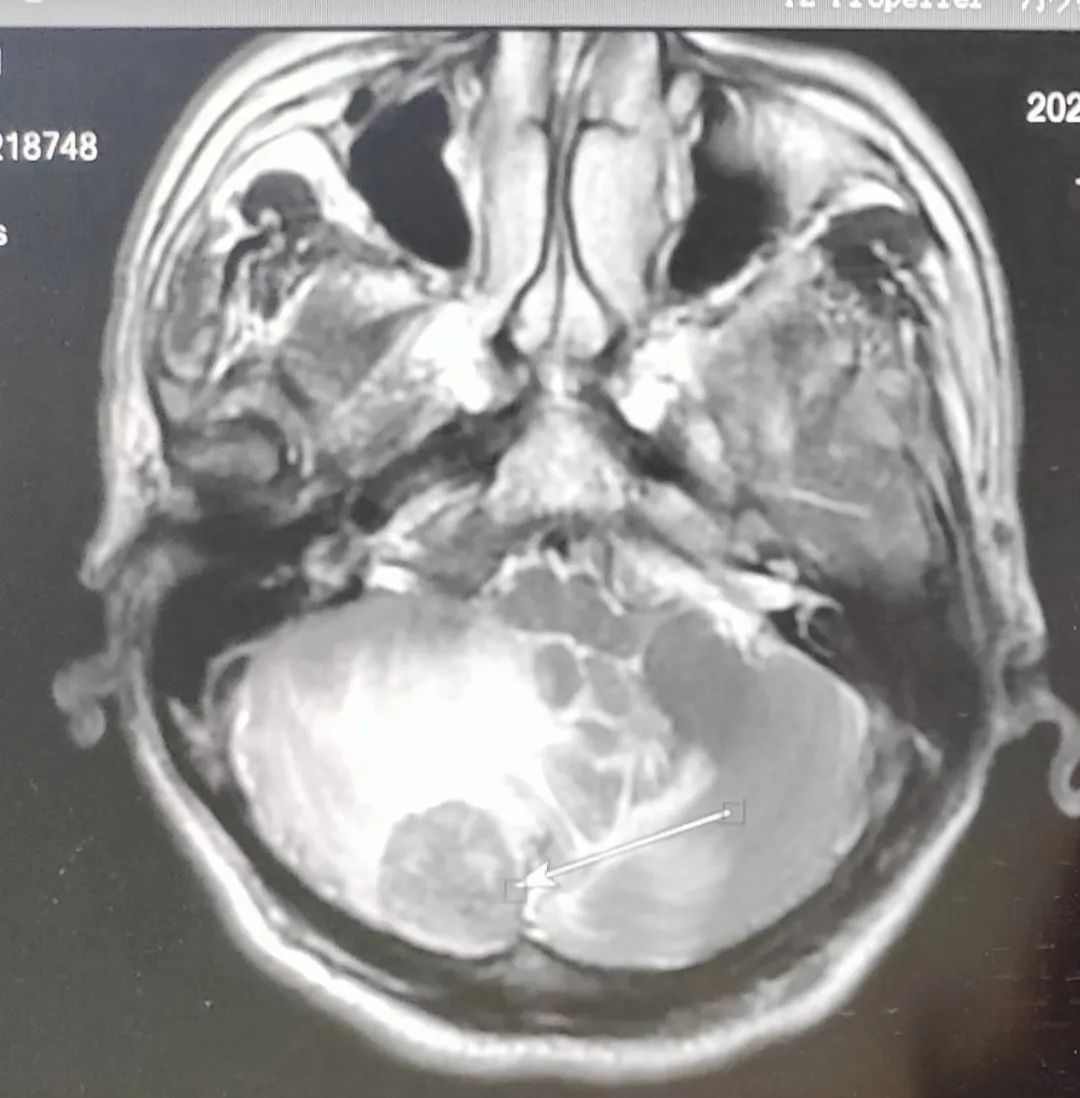

患者林女士,2023年7月确诊为肺癌晚期。由于病灶压迫肺门及大血管,无法进行手术治疗,化疗后出现耐药,于10月份发现脑部转移,对于病情快速恶化的林女士犹如雪上加霜。我院肿瘤放疗科陈春荣医生结合患者病情,采取个体化精准放疗及综合治疗。经过两月余治疗后,患者病情得到了有效控制,对生活再次充满信心。

头部调强放疗前后对比图